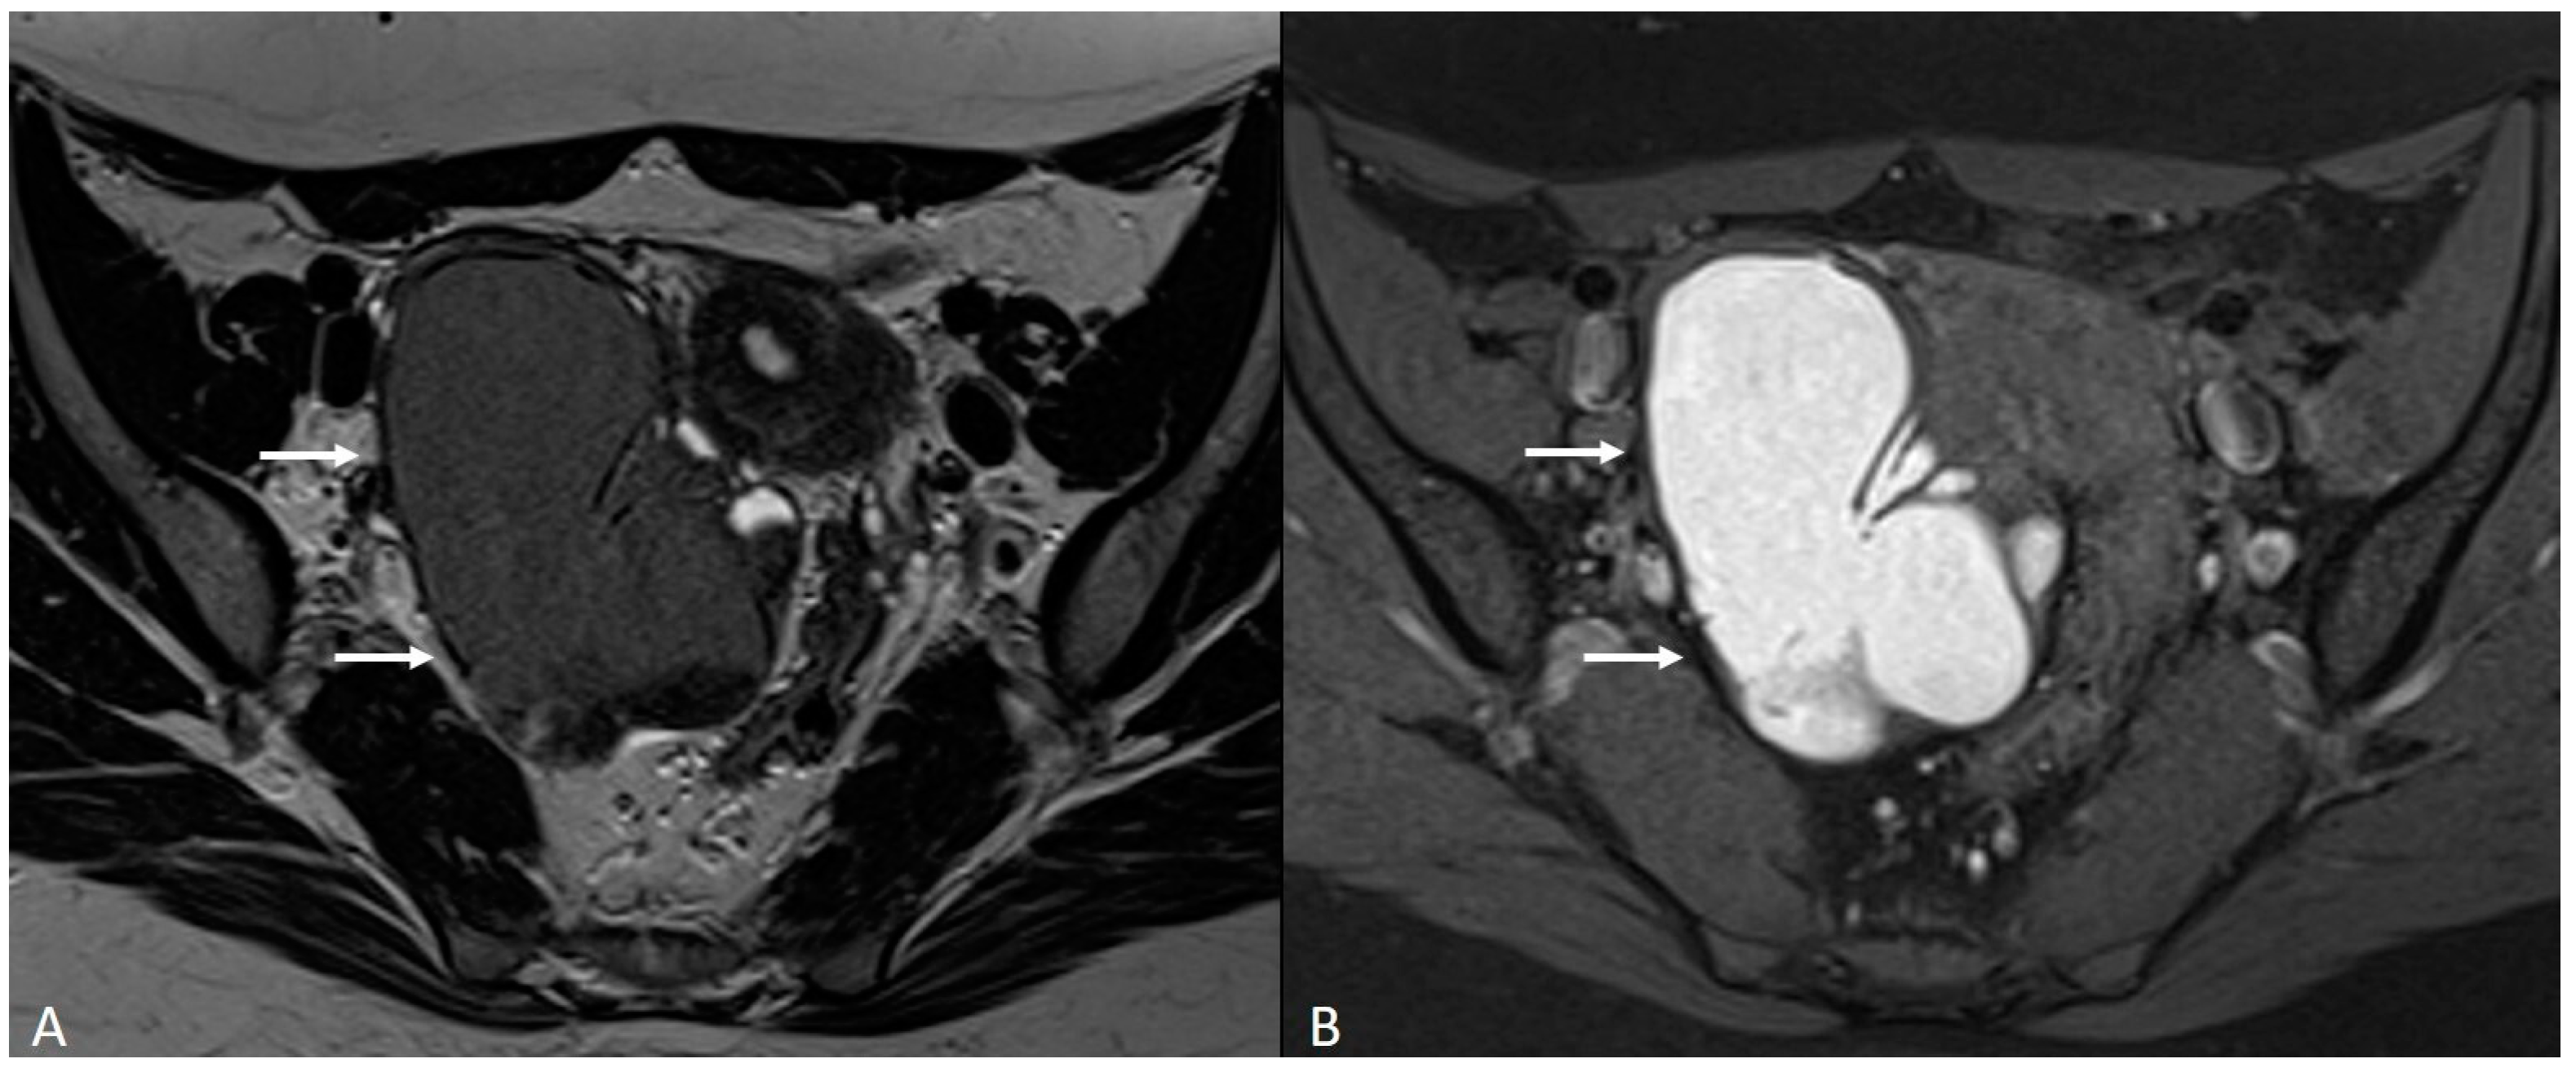

In other cases, the involvement of the round ligament can be appreciated as irregular contours with a nodular aspect [43] (Figure 2).

Figure 2.

Deep infiltrating endometriosis of the anterior and posterior compartments in 33-year-old female with dysmenorrhea, chronic pelvic pain, dyspareunia and dyschezia. (A) Sagittal T2WI. Evidence of external anterior adenomyosis and plaque of the vesico-uterine pouch (white arrow); (B) Sagittal T2WI. Retrocervical localization of DIE (white arrow); (C) Axial T2WI. Left uterosacral ligament (USL) localization (white arrowhead), plaque of vesico-uterine pouch (white arrow) with involvement of the round ligaments, particularly on the left (white dotted arrows), and adhesions with the ovaries (retraction of the broad ligaments).

The surgical approach can vary according to the proximal or distal involvement [39].

Involvement of the proximal portion of ligaments (distance less than 2 cm from the cervix) may, in some cases, be associated with thickening at the level of the torus uterinus; in such cases, it is essential to report any mass or thickening in the upper portion of the posterior cervix, as this could cause the surgeon to proceed with a laparoscopic trans-vaginal approach [7] (Figure 2, Figure 3 and Figure 4).

Figure 3.

Right uterosacral ligament localization in a 43-year-old female. The right uterosacral ligament appears thickened at uterine insertion (white arrow).

Figure 4.

Retrocervical endometriosis plaque, intestinal localization, kissing ovaries with bilateral ovarian endometriomas. (A,B) Axial T2WI; (C) Coronal T2WI. Hypointense retrocervical plaque (white arrowhead in (A)) localized in the uterine torus with involvement of the utero-sacral ligaments. Adhesions involve both ovaries with bilateral endometriomas (white arrows), which are prolapsed in a retro-uterine position and adhered to the utero-sacral ligaments and the recto-sigmoid junction. There is also an eccentric anterior parietal thickening in the recto-sigmoid junction suggestive of intestinal endometriosis lesion (white dotted arrow in (A)).